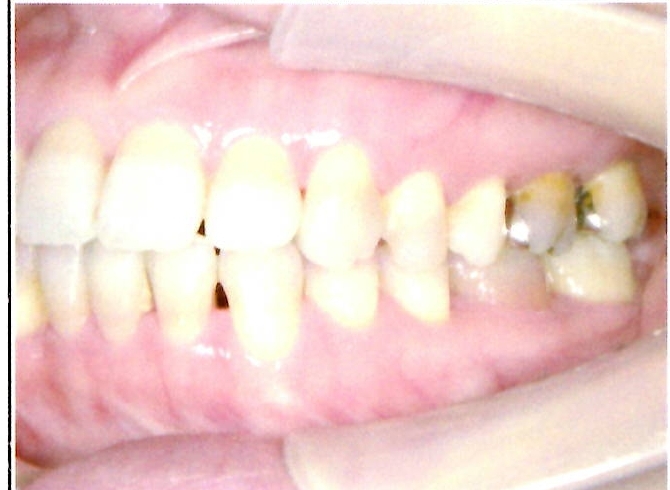

| 主訴・治療前の状態 | 前歯が噛み合っていない状態(開咬傾向)で、犬歯がやや前方に突出しており、見た目にお悩みがありました。 |

| 治療内容 | 上下左右の第一小臼歯(4番)計4本を抜歯し、そのスペースを利用して歯列を整え、前歯の噛み合わせを改善しました。 |

| 治療結果 | 前歯がしっかり噛み合うようになり、見た目も美しく整いました。患者様の満足度が非常に高かった症例です。 |